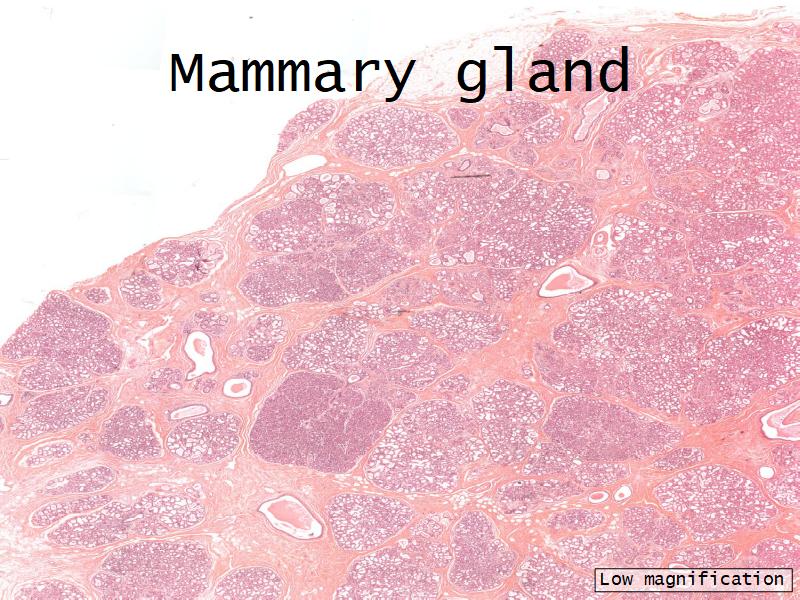

Slides

- Mammary gland - slide 57

Mammary gland

Write short notes describing the structure of the mammary gland.

Mammary gland

- Compound tubuloalveolar gland

- 12 - 20 glands

- Each with own lactiferous duct

- Each with own lactiferous sinus

- Opens on skin at apex of nipple

Structures

List the structures and cells found in the mammary gland.

Structures

- Lactiferous sinuses

- Stratified squamous near opening on skin

- Stratified cuboidal other parts

- Lactiferous ducts

- Stratified cuboidal

- Myoepithelial cells

- Underlie lactiferous ducts in most areas

- Basal lamina

- Separate epithelial components from stroma

Active gland

- Much larger than resting phase

- Terminal ducts proliferate to form alveoli

- Alveoli

- Surrounded by incomplete myoepithelial cells

Alveolar cells

- Apocrine secretion

- Active state

- Resting state